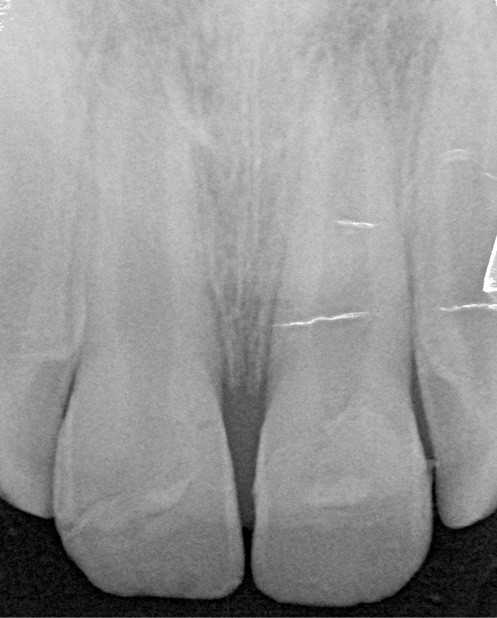

L’examen radiologique montre que les racines de 11 et 21 ne sont pas totalement édifiées (fig. 3). La priorité sera alors de conserver la vitalité pulpaire de ces dents immatures.